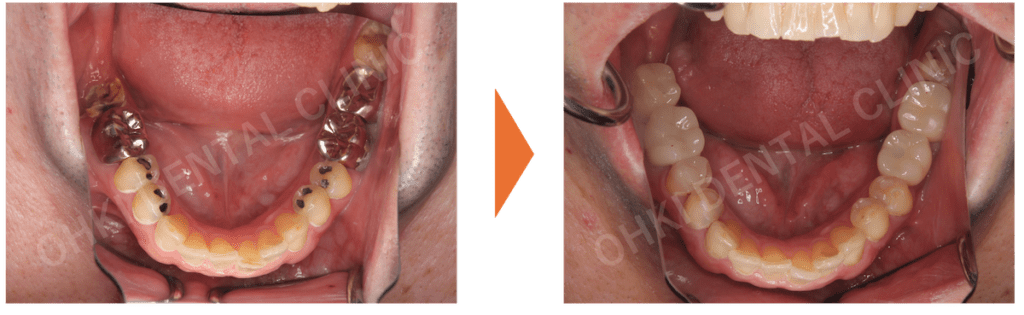

Before / After の比較:

治療前と比べて、上の前歯の正中離開(スキッパ)は改善されました。

仕上がりの特徴

- インプラントを埋入したことにより、噛む機能が回復したことが大きな結果です。

- 噛み合わせの柱が再建されたことで、今後、残存している歯の破折リスクや負担が軽減されました。

- 歯が抜けたままの状態ではなく、天然歯に似た形態でセラミック素材の上部構造を作製したため、見た目(審美面)も改善し、歯が再生したような状態を実現できました。